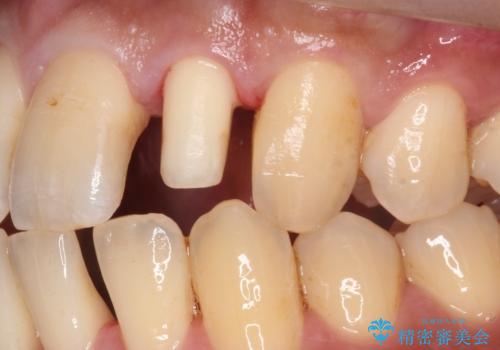

- 左の前歯が黒いとのことで来院。

1番目の歯は小さい虫歯があったのでプラスチックの樹脂で治療をしました(保険内)。

2番目の歯は二箇所虫歯があり、プラスチックの樹脂で治療するとつぎはぎみたいになってしまうので、

白い被せ物(ジルコニアクラウン)で治療しました。